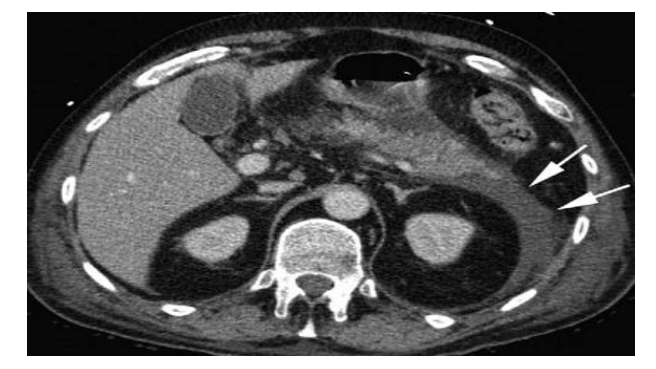

Tratamento da Necrose Infectada

A suspeita ocorre por piora clínica (“segunda onda”) após 7-10 dias ou gás na TC.

- Antibiótico: Carbapenêmicos ou Quinolonas (penetram no tecido pancreático).

- Step-up Approach: Começar com o menos invasivo.

- Drenagem Percutânea ou Endoscópica.

- Se falhar: Necrosectomia minimamente invasiva (VARD ou endoscópica).

- Último caso: Necrosectomia aberta (alta morbidade).